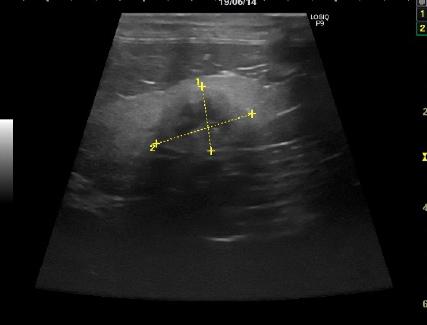

| ケース | 18歳、去勢済男の子のネコちゃん |

| 症状 | 食欲不振と嘔吐で来院されました。血液検査を行ったところ、腎臓の数値の増加が認められました。レントゲン検査ならびにエコー検査において右尿管結石による尿管閉塞が疑われました。 |

| 手術方法 | 尿管閉塞が認められた場合、1,尿管切開による結石摘出術 2,尿管の一部を切除し膀胱と吻合する尿管膀胱吻合術 3、人工尿管を用いた腎臓皮下尿管バイパス手術 4,尿管ステント挿入 5,一時的な腎瘻チューブ設置術などがあります。それぞれの手術方法には一長一短があります。今回はまだ年齢も若く飼い主様のご意向により、尿管切開による結石の摘出を行いました。 |

| 術後経過 | 術後、水腎は解消し腎臓の数値も低下し順調に排尿が認められました。 |

| 図1 | 図2 | 図3 |